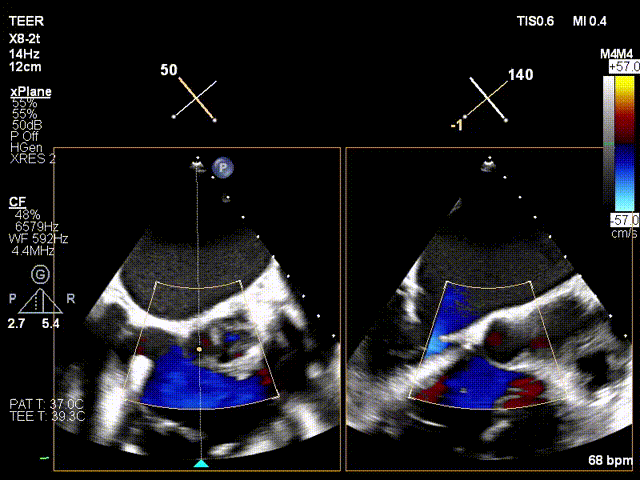

Regurgitation Outcome:

Critical regurgitation (5+) reduced to moderate to severe regurgitation (3+).

Preoperative critical regurgitation (5+)

Postoperative moderate to severe regurgitation (3+)